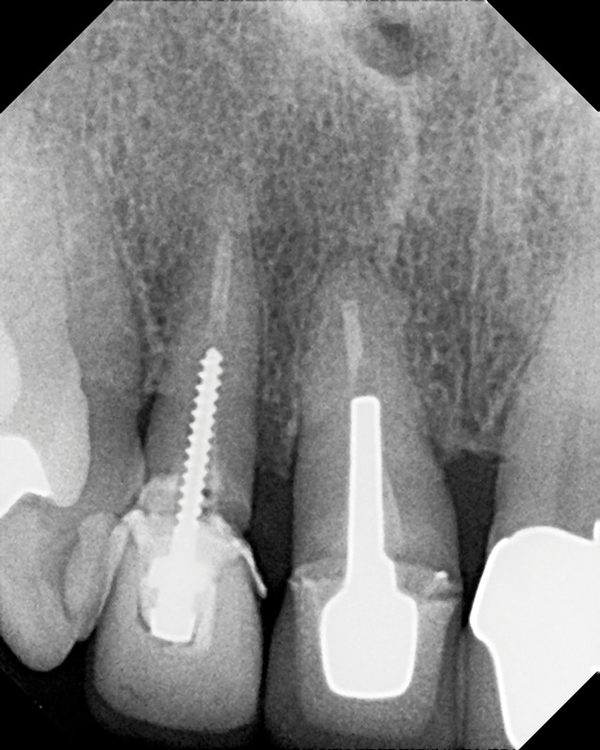

Question 4: Which options cannot be seen in the print of the X ray?